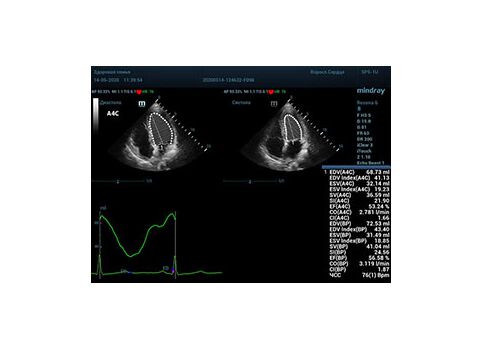

С появлением В режима реализовалась возможность визуализации всех сегментов миокарда из парастернальных и апикальных сечений. Метод Teicholtz в широкой практике сменился методом дисков. Метод дисков, или метод Simpson, позволяет разбить левый желудочек на 20 дисков, с расчетом объема каждого из них. Используя 2 перпендикулярных сечения, апикальные двух и четырех камерное, мы приближаемся к значению реального объема левого желудочка. Исследователь обводит интерфейс эндокард – кровь в фазу диастолы и фазу систолы. Линия простирается от кольца митрального клапана и до кольца митрального клапана, четко разграничивая объем желудочка от предсердия. Для достоверного изменения необходимо использовать ЭКГ канал.

Что могут предложить современные приборы? Приборы нашего времени являются мощными вычислительными машинами, способными обрабатывать полученную информацию даже без помощи человека. Система автоматического вычисления фракции выброса – AUTO EF на приборах серии Resona компании Mindray сделает все за вас. За пару секунд прибор сам отыщет нужную фазу сердечного цикла и произведёт измерение и расчеты, а также покажет график изменения объема в сердечном цикле. От Вас требуется только получить качественное 4С и 2С сечение. Впрочем, прибор всегда оставляет возможность коррекции, если доктор имеет свое мнение на расположение точек планиметрии или момента измерения по ЭКГ каналу.